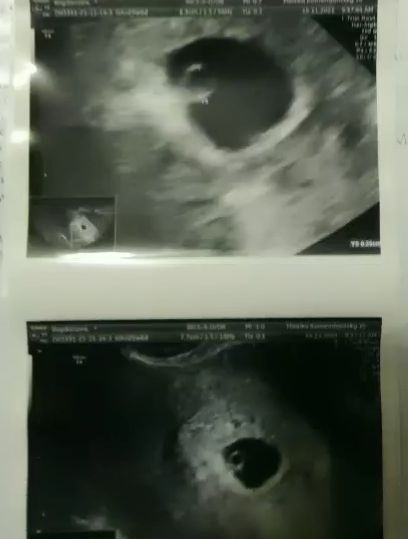

При беременности ПЯ находится ВНУТРИ матки, а не в её стенках). И там не черные точки, когда беременность, там кружочек,как пузырёк. узист бы уж явно понял)))

вот для наглядности снимок узи с плодным яйцом